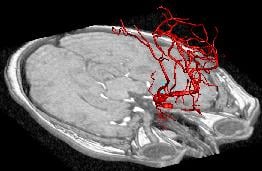

NECStR has been fully operational since May 3 2007 with a special focus is on image guided interventions for minimally invasive treatment of vascular disease. The center’s expertise and resources enable animal modeling of vascular pathologies, 3D x-ray imaging, post acquisition image processing, rapid prototyping from medical imaging and image guided minimally invasive surgery. Although the center’s focus lies in cardiovascular imaging and intervention, previous work has included selective vascular drug delivery for cancer treatment and orthopedic device implantation.